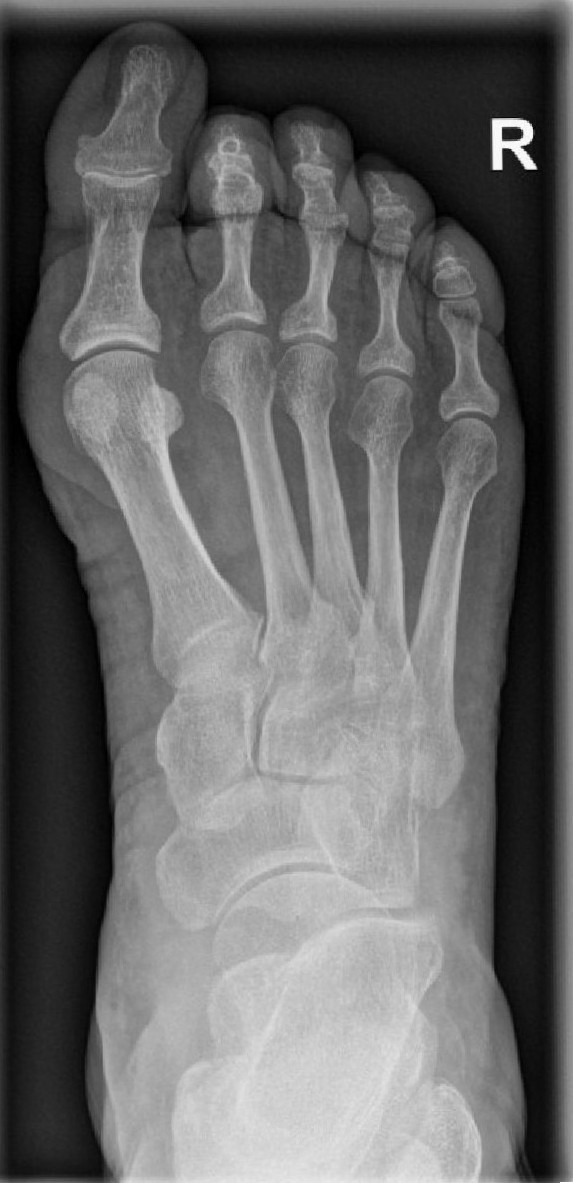

Der Hallux valgus ist eine Deformität des Vorfußes, bei der die Mittelfußköpfchen auseinanderweichen. Dabei verschiebt sich insbesondere das erste Mittelfußköpfchen in Richtung Körpermitte, während der Großzeh gleichzeitig nach außen abweicht. Das führt zu einer Insuffizienz des Bandapparates im Vorfuß und der typischen Hallux valgus-Fehlstellung. Diese geht vor allem mit belastungsabhängigen Schmerzen, Druckstellen und Problemen bei der Schuhversorgung einher. Ursachen für den Hallux valgus können unter anderem angeborene Faktoren sowie falsches, einengendes Schuhwerk oder Fehlbelastungen sein.

Um festzustellen, ob eine Hallux valgus-Deformität vorliegt, erfolgen zunächst ein Anamnesegespräch sowie eine ausführliche Untersuchung beider Füße in stehender Position. Häufig ist die Erkrankung dabei schon deutlich zu erkennen. Zur Planung der Therapie kommen darüber hinaus Röntgenaufnahmen des betroffenen Fußes zum Einsatz. Eine Schnittbilddiagnostik (CT, MRT) ist in der Regel nicht erforderlich.

Für die Behandlung eines Hallux valgus stehen je nach Ausmaß der Erkrankung verschiedene Operationstechniken zur Verfügung: Im einfachsten Fall lassen sich das Köpfchen des ersten Mittelfußknochens verschieben (Osteotomie) und Weichteilschäden operativ korrigieren.